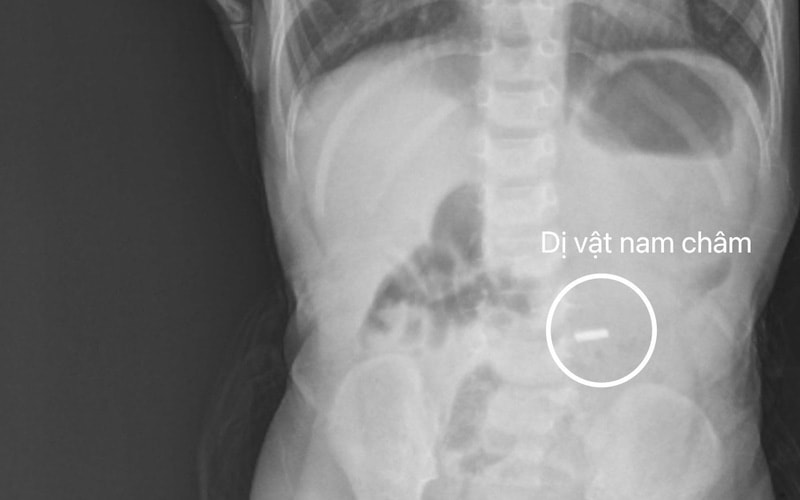

Gắp dị vật nam châm ở tá tràng cho bé trai 18 tháng tuổi

PLBĐ - Sau khi được các bác sĩ thăm khám và chụp X-quang, xác định có hình ảnh dị vật cản quang nằm trong tá tràng, bệnh nhi được chuyển đến Trung tâm Nội soi để tiến hành nội soi cấp cứu, gắp dị vật là nam châm kích thước 6x6mm tại tá tràng D2 ra ngoài.